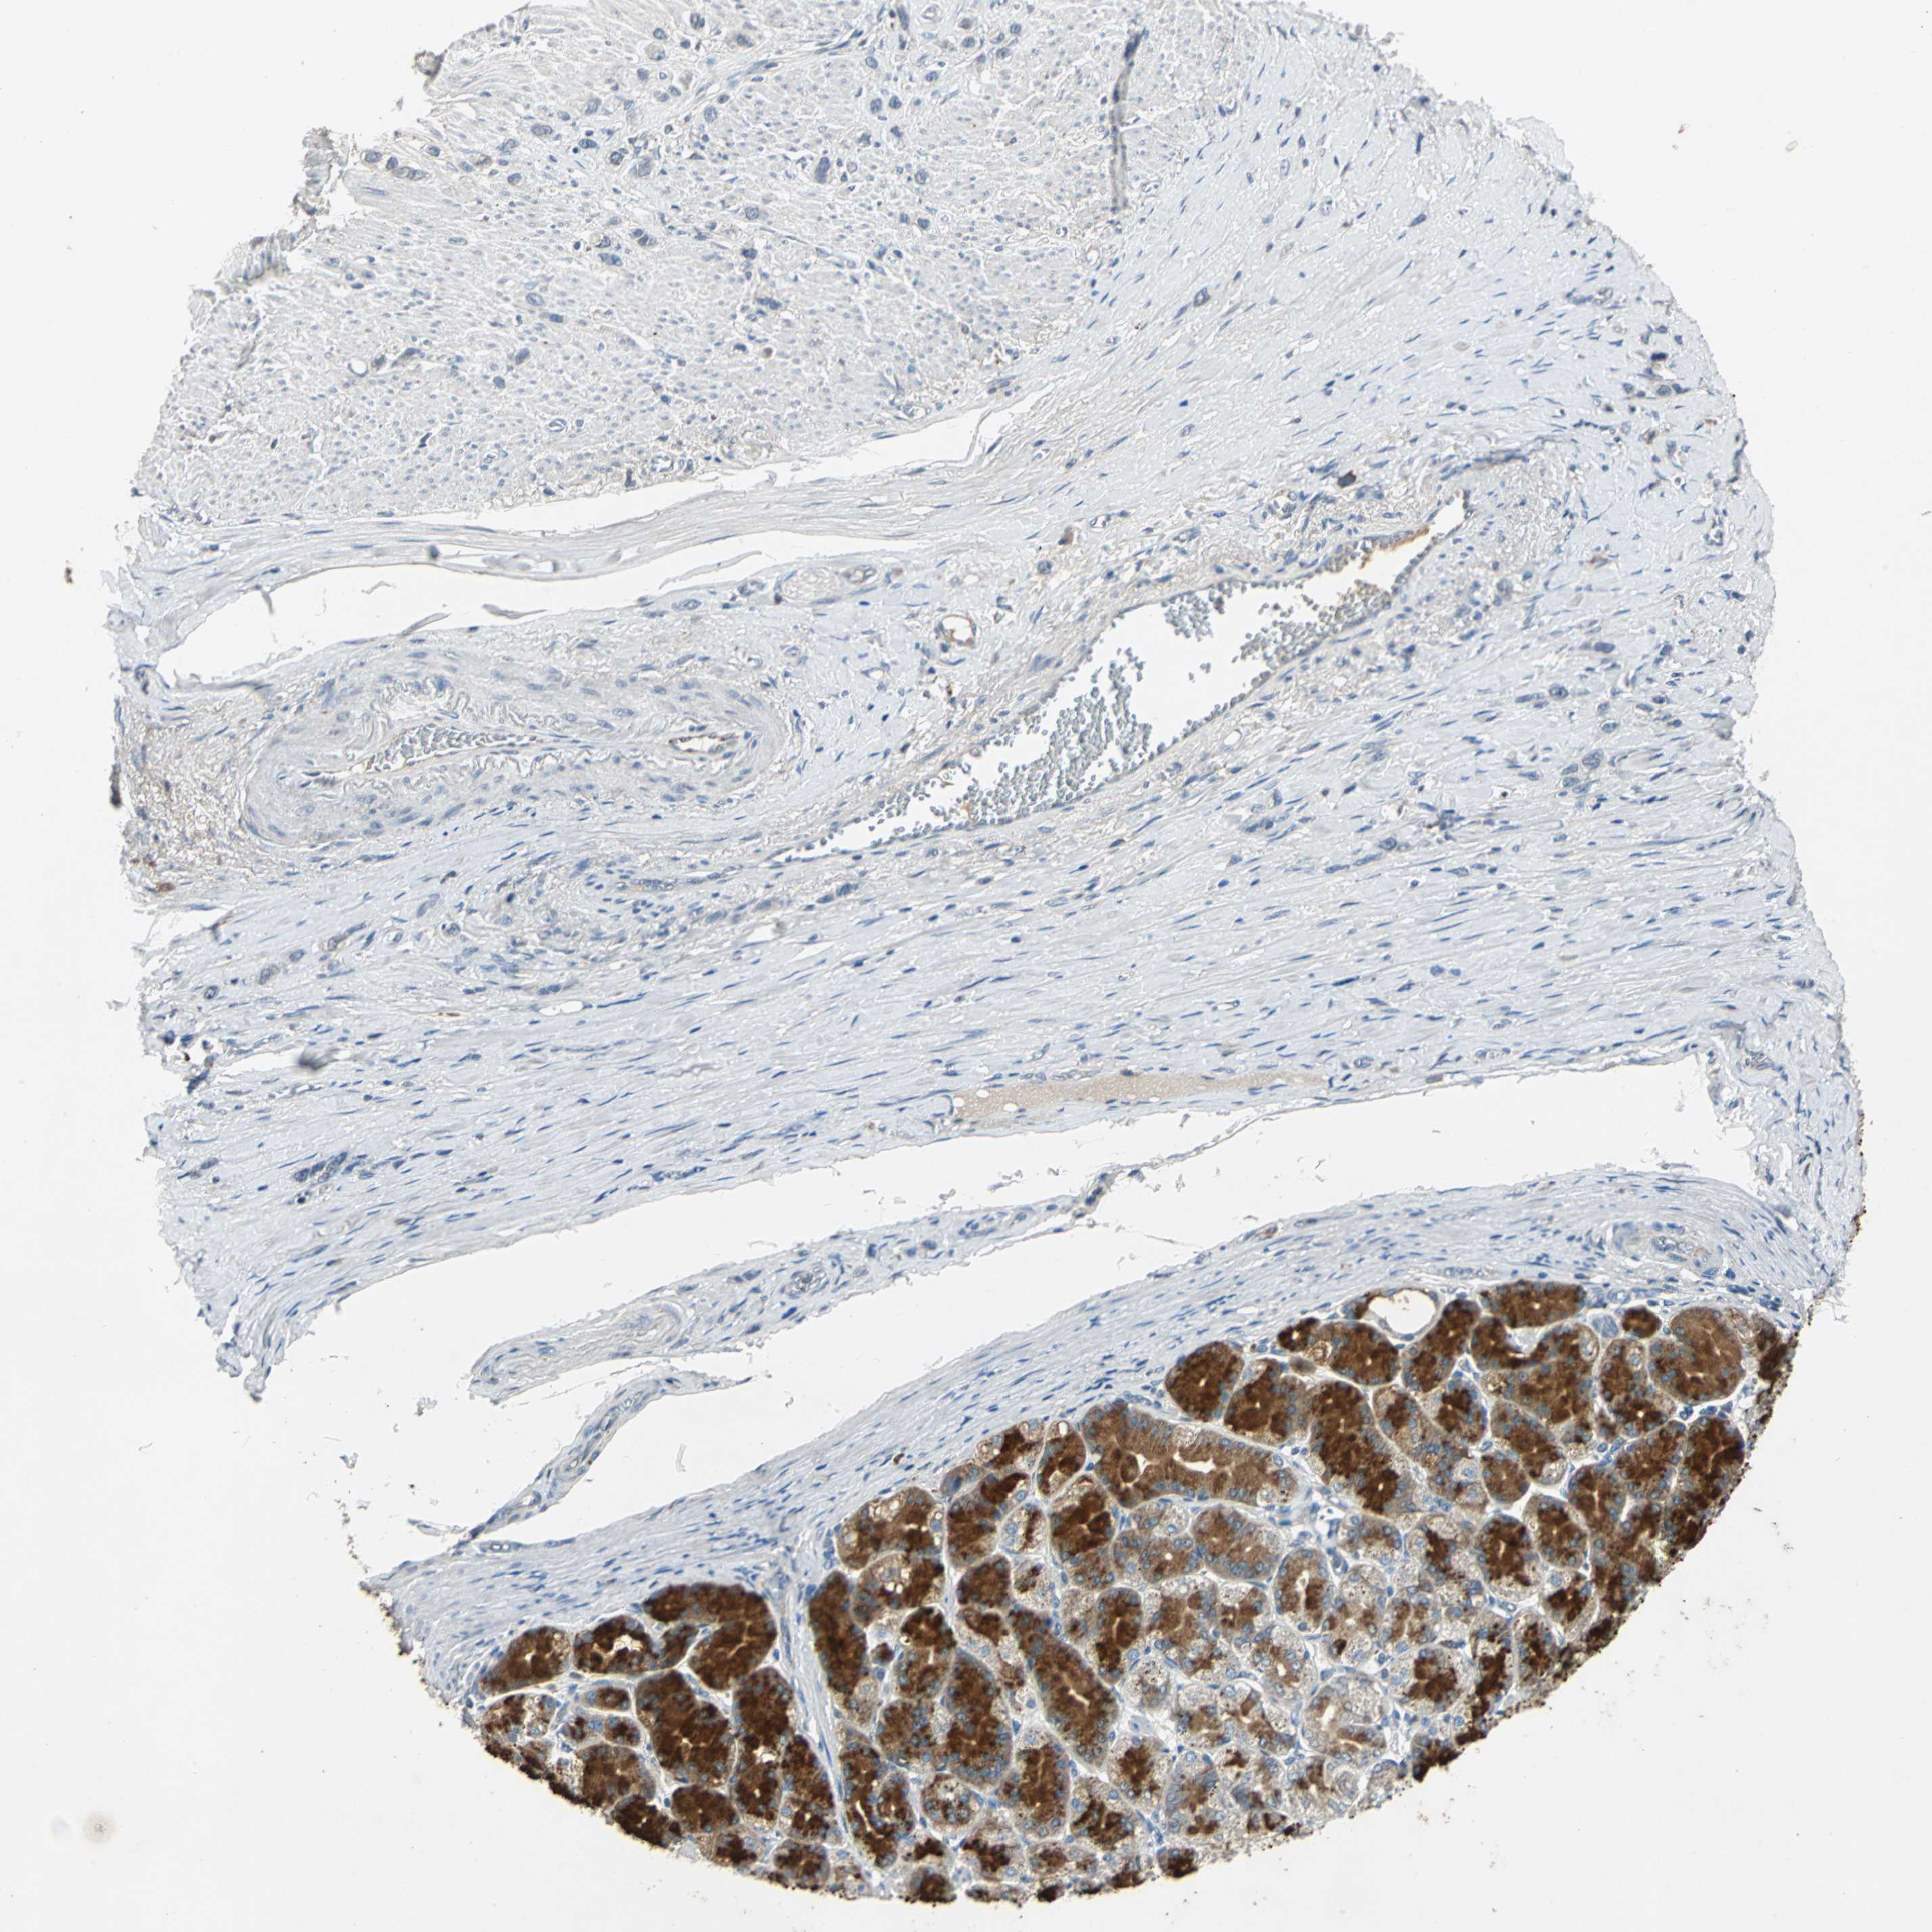

STOMACH CANCER - Protein expressioni

A mouse-over function shows sample information and annotation data. Click on an image to view it in a full screen mode. Samples can be filtered based on level of antibody staining by selecting one or several of the following categories: high, medium, low and not detected. The assay and annotation is described here.

Note that samples used for immunohistochemistry by the Human Protein Atlas do not correspond to samples in the TCGA dataset.

Antibody stainingi

Antibody staining in the annotated cell types in the current human tissue is reported as not detected, low, medium, or high, based on conventional immunohistochemistry profiling in selected tissues. This score is based on the combination of the staining intensity and fraction of stained cells.

Each image is clickable and will lead to virtual microscopy that enables deeper exploration of all samples and also displays staining intensity scores, fraction scores and subcellular localization as well as patient and tissue information for each sample.

Antibody HPA006584

Antibody HPA061679

Staining

High

Medium

Low

Not detected

Intensity

Strong

Moderate

Weak

Negative

Quantity

>75%

75%-25%

<25%

None

Location

Nuclear

Cytoplasmic/membranous

Cytoplasmic/membranous,nuclear

Adenocarcinoma, NOS

Adenocarcinoma, High grade